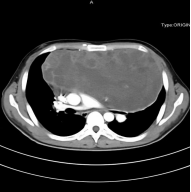

该患者去年8月突发胸闷于当地医院就诊,胸部CT发现了前纵隔巨大占位,大小约15.3cm×14.2cm。患者于当地医院进行穿刺确诊为“生殖细胞瘤”后进行3周期化疗,但是化疗后复查CT发现肿瘤进行性长大,今年2月前复查CT提示纵隔肿瘤最大截面“20.4cm×16.1cm”。患者心脏及纵隔大血管受压明显,本来位于左侧的心脏,被肿瘤挤压到了右侧胸腔,且出现了严重的呼吸系统和循环系统受累。跑遍各地多次求医无果后,患者及家属抱着最后一线希望找到我院肺癌中心周清华教授。

图1:患者术前胸部增强CT显示前纵隔巨大肿瘤